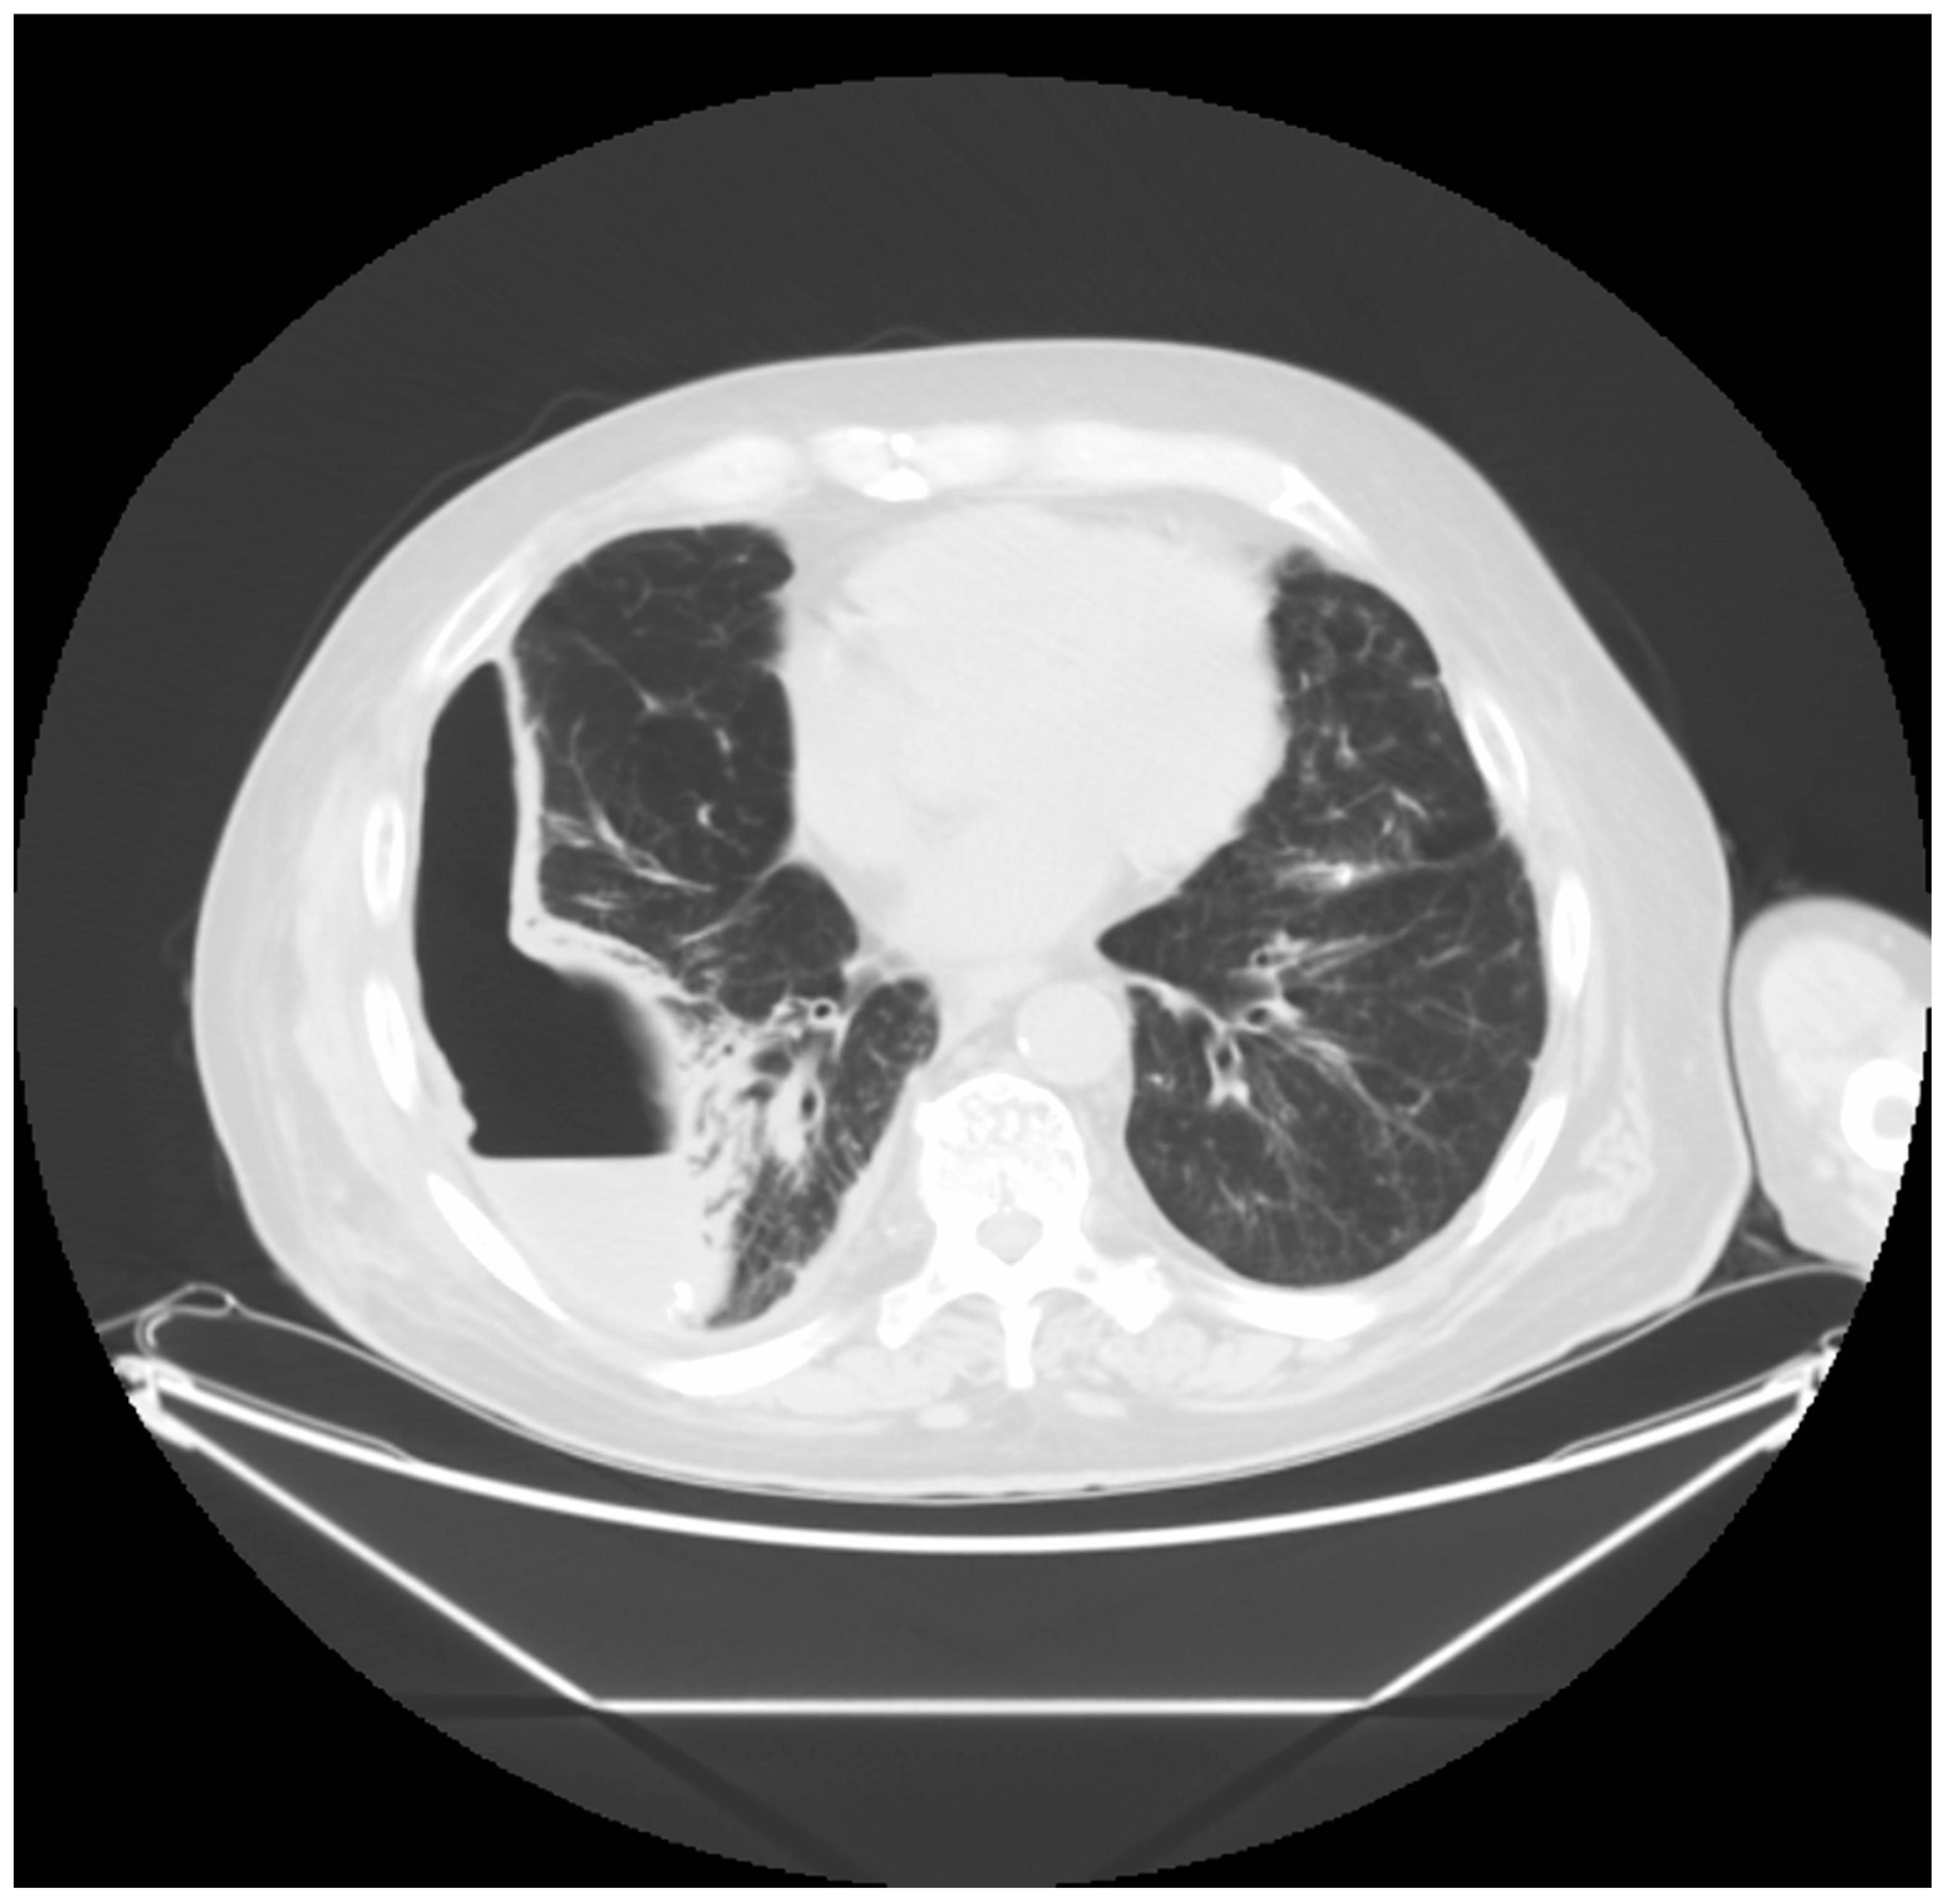

2. Case Presentation